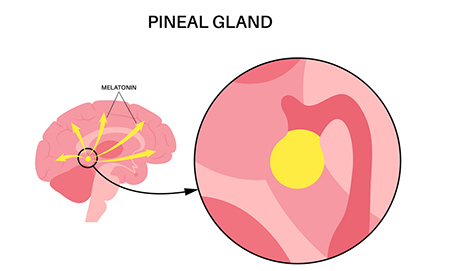

غده صنوبری به شکل مخروط کاج است و به اندازه یک نخود است و قطر آن تقریباً 8 میلی متر است. در اپیتالاموس، ناحیه ای از مغز که بین دو نیمکره قرار دارد و توسط تالاموس احاطه شده است، قرار دارد. غده صنوبری از پینهآلوسیتها تشکیل شده است که سلولهای تخصصی هستند که ملاتونین، هورمونی که چرخه خواب و بیداری را تنظیم میکند، تولید و ترشح میکنند.

تولید ملاتونین توسط بخشی از مغز به نام هسته سوپراکیاسماتیک (SCN) که در هیپوتالاموس قرار دارد، کنترل می شود. SCN اطلاعات مربوط به چرخه های نور و تاریکی را از چشم دریافت می کند و سیگنال هایی را برای تنظیم تولید ملاتونین به غده صنوبری ارسال می کند. در طول روز، زمانی که نور بیشتری وجود دارد، SCN سیگنال هایی را برای سرکوب تولید ملاتونین ارسال می کند. در شب، زمانی که نور کمتری وجود دارد، SCN سیگنال هایی را برای تحریک تولید ملاتونین ارسال می کند که به بهبود خواب کمک می کند.

غده صنوبری علاوه بر نقشی که در تنظیم چرخه خواب و بیداری دارد، در تنظیم خلق و خو و رشد جنسی نیز نقش دارد. مطالعات نشان داده اند که افراد مبتلا به افسردگی و سایر اختلالات خلقی سطوح پایین تری از ملاتونین دارند که نشان می دهد غده صنوبری ممکن است در این شرایط نقش داشته باشد. غده صنوبری همچنین با تولید سطوح بالاتر ملاتونین در دوران کودکی و سطوح پایین تر در دوران نوجوانی به تنظیم شروع بلوغ کمک می کند.